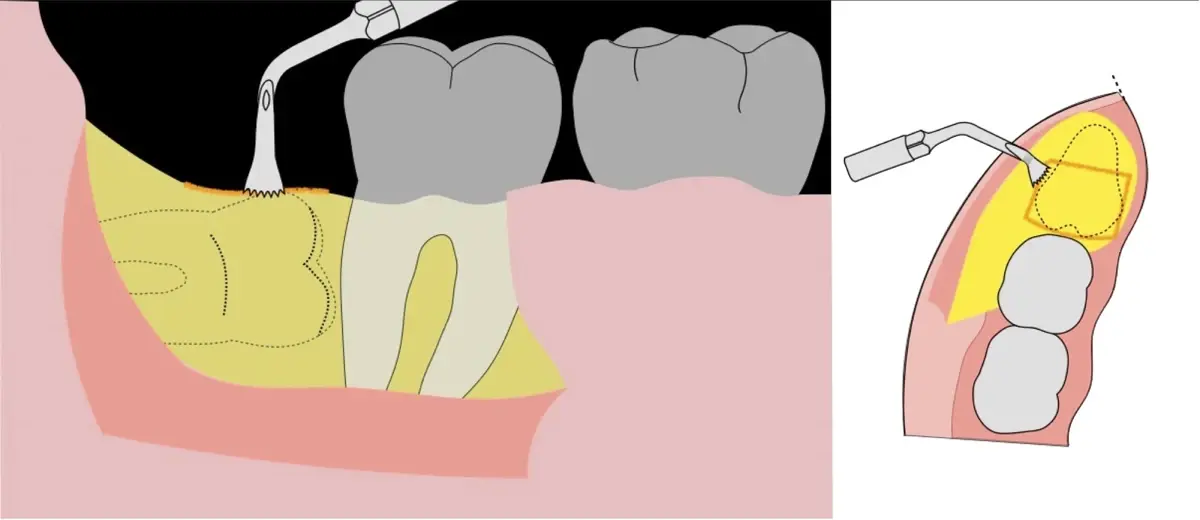

Figura 7. Eliminación del fragmento vestibular.

Figura 8. Odontosección mediante fresa de alta rotación y/o inserto de corte de piezoeléctrico. Posteriormente se procede al ensanchamiento del espacio pericoronario con el periótomo de piezoeléctrico para facilitar la avulsión de la pieza dentaria.